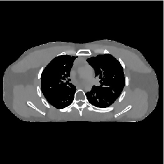

For a 3D cone-beam CT problem, circulant preconditioning is less accurate because the matrix is inherently shift-variant due to the system geometry and/or spatial variations in detector response [44]. Despite this fact, we select a circulant preconditioner to approximate in (4), and solve (2) in 3D CT reconstruction using more PCG inner iterations. The reason is three fold. First, a circulant preconditioner is still one of the classical options to approximate a shift-variant matrix (e.g., ) and accelerate CG (see, for example, [44, 45]). Second, effective learned transforms are generally close to orthogonal (the same applies to the 2D case), and a scaled identity preconditioner can approximate the term . Third, a few PCG iterations in Algorithm 1 can provide fast convergence: 1) Fig. 2 shows that and PCG iterations give very similar convergence rates; 2) in the 3D CT reconstruction, the convergence rates of Algorithm 1 are comparable to those provided in 2D CT reconstruction – see Fig. 5. More sophisticated preconditioners might provide faster convergence [46, 47].

III-B2 Algorithm Convergence Rate

Our main concern in convergence rates of Algorithm 1 lies with an inaccurate preconditioner (e.g., circulant one) particularly for the 3D sparse-view CT reconstructions. To see the effects of using a loose preconditioner in Algorithm 1, we compared the convergence rates of the 3D case with those of 2D (Fig. 5(a) and Fig. 5(b)). In the first iterations, Algorithm 1 converges faster in 2D experiments than 3D experiments. However, after iterations, the convergence rates of Algorithm 1 are similar in both 2D and 3D reconstructions. In addition, more PCG (with a circulant preconditioner) iterations does not significantly accelerate Algorithm 1 (see Fig 2). These empirically observations imply that, in the 3D sparse-view CT reconstructions, Algorithm 1 using a circulant preconditioner ( PCG iterations) is a reasonable choice.